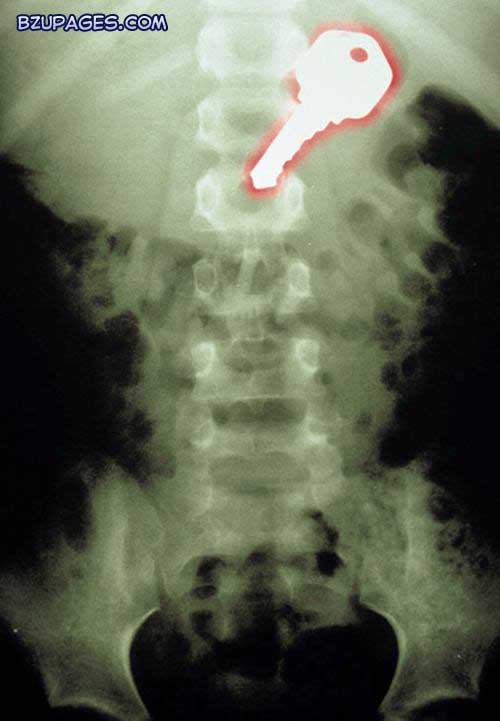

Attachment 21981

A coloured X-ray of a key (outlined in red, top right) swallowed by a 7-year-old boy